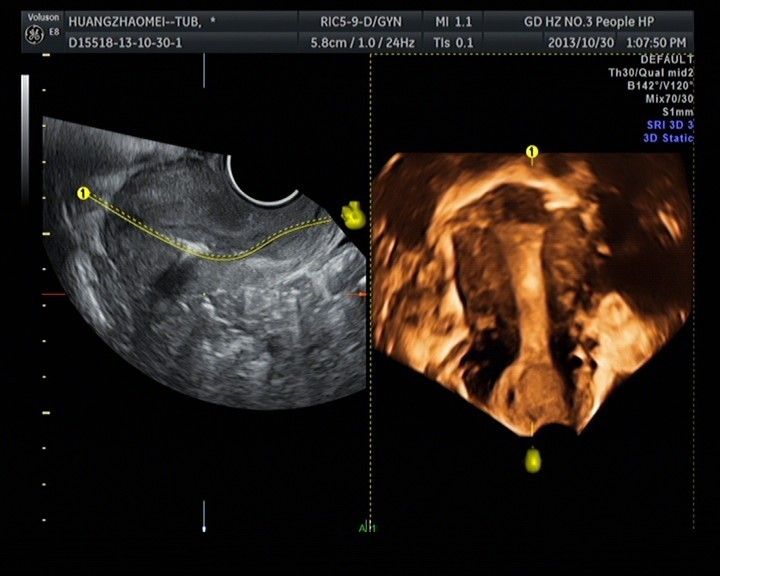

我院超聲科成功開展子宮輸卵管超聲造影

隨著超聲醫(yī)療技術(shù)的發(fā)展日新月異,超聲在臨床中不再只充當(dāng)輔助診斷的角色,也漸漸進入了臨床治療階段,應(yīng)用范圍不斷擴展。1030日上午,我院超聲科馬曉芹主任帶領(lǐng)自己的團隊包括王瑤、邱藝瓊、楊君梅等醫(yī)生以及在婦產(chǎn)科王主任、盛主任、葉穎菲醫(yī)生的大力支持配合下成功完成開展了首例子宮、輸卵管超聲造影術(shù)。這將是我院超聲科發(fā)展史上的一個重要里程碑,同時也標(biāo)志著我院婦產(chǎn)科在不孕不育的診斷方面上升到了一個新的臺階。

隨著四維超聲技術(shù)的成熟,隨著SonoVue 造影劑的誕生,經(jīng)陰道四維超聲聯(lián)合應(yīng)用SonoVue 超聲造影檢查子宮、輸卵管的技術(shù)也應(yīng)運而生。子宮輸卵管超聲造影術(shù)具有無放射性、不需特殊環(huán)境、無過敏反應(yīng)、可重復(fù)檢查、無損傷性、安全、價廉等優(yōu)點,容易顯示輸卵管全程、對輸卵管盤曲或成角的判斷更精確,降低操作依賴性,操作簡便,圖像直觀,便于臨床醫(yī)師觀察。這既彌補了以往輸卵管通液術(shù)的主觀性較大、準(zhǔn)確性較差等不足,更避免了X 線子宮輸卵管碘油造影(HSG)的射線輻射、碘油過敏以及腹()腔鏡檢查有創(chuàng)傷高風(fēng)險等缺點。

目前,我院超聲科已具備實施該項檢查的設(shè)備及臨床技術(shù)支持。它通過宮腔內(nèi)注射SonoVue 超聲造影使宮腔及輸卵管顯影,可清楚觀察到宮腔、宮角、雙側(cè)輸卵管全程的形態(tài)及與卵巢的位置關(guān)系。子宮輸卵管超聲造影術(shù)的成功開展,將大大解除不孕患者的痛苦及消除他們的心理陰影,真正地給每一對不孕夫婦帶來福音、帶來家庭的幸福! 超聲科 馬李明)